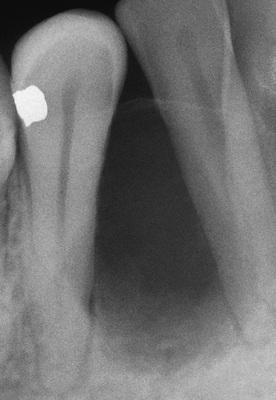

Radiolucent lesion involving an unerupted mandibular first premolar. In contrast to the usual dentigerous cyst, the radiolucency extends almost to the apex of the tooth.

adenomatoid odontogenic tumor